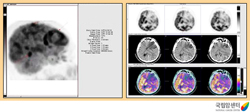

양전자방출단층촬영술(PET)을 이용한 전이성 뇌종양의 진단

2009.08.21